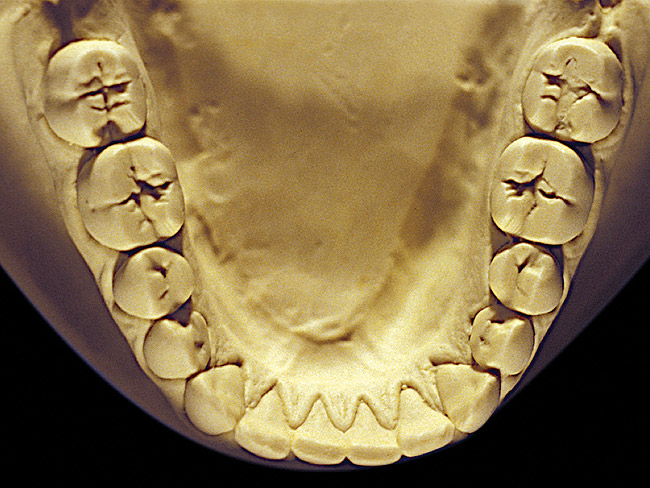

Figure 8  Moderate NCLTS from toothpaste, mandibular arch.

Figure 8

Figure 7 and Figure 8 are examples of NCLTS resulting from toothpaste. Upon examination, one could see that the overall anatomical detail of the teeth was faded with a sandblasted appearance. A closer view of the facial surfaces (Figure 9 and Figure 10) illustrates this to a greater degree and one can observe that the normal intricate facial anatomy was completely missing. It is interesting to note there was no cervical recession of the gingiva, even though every surface of every tooth had been abraded. This is due to the fact that this patient had always used a soft, round-ended filament toothbrush.21-22 This patient's sole desire regarding her oral hygiene was to get her teeth whiter.